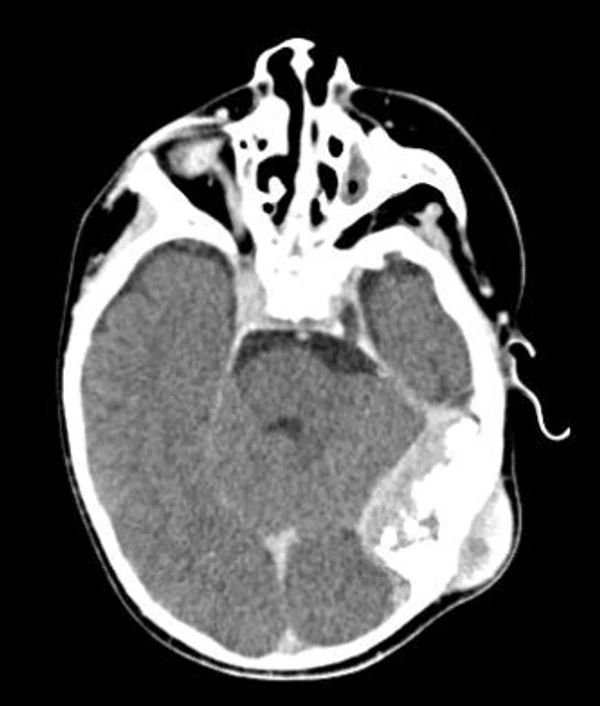

Удаление опухолей черепаВ качестве примера лечения пациентов с опухолями черепа привожу личное наблюдение пациента грудного возраста с опухолью черепа. В возрасте 1 мес. у ребёнка в затылочной области слева родителями обнаружено плотное образование диаметром 5 мм. За 3 мес. до госпитализации образование значительно увеличилось в размерах. При поступлении в возрасте 6 мес. в затылочной области слева (в проекции лямбдовидного шва) имеется безболезненное, плотное, неподвижное, бугристое образование размерами 5 х 4 х 2 см. При КТ и МРТ головы выявлена опухоль черепа в области астериона слева, обладающая преимущественно интракраниальным ростом (рис. 30 а). Ребёнку выполнено удаление опухоли черепа (рис. 30 б). Образовавшийся дефект черепа больших размеров закрыт перфорированной титановой пластиной (рис. 30 в). При наблюдении пациента в течении 2-х лет рецидива заболевания и деформации черепа не отмечалось.